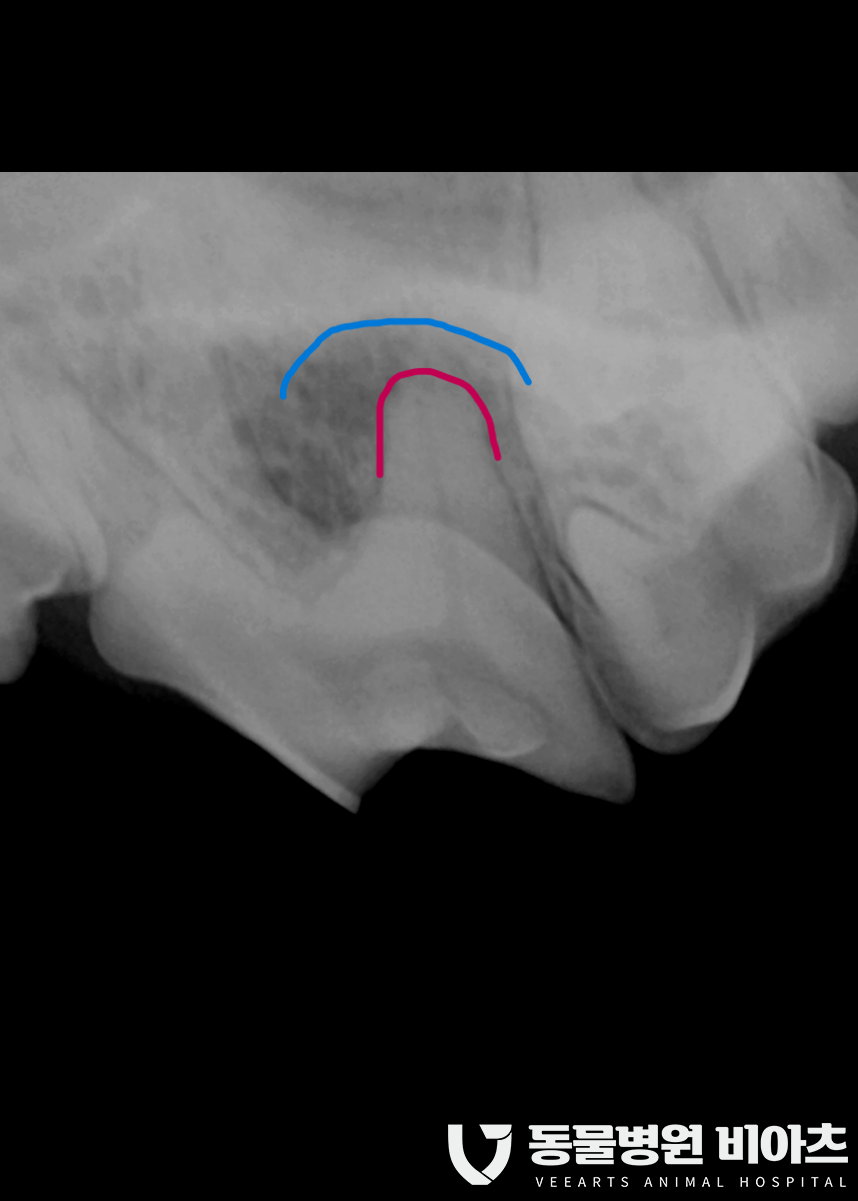

치과 방사선 촬영에서 치아 뿌리 주변에

동그랗고 까만 병변으로 확인되며

빨간색의 치근단(치아 뿌리) 위쪽에

빨간색과 파란색의 사이에

검은색의 농이 차 있는 것을 확인할 수 있습니다.